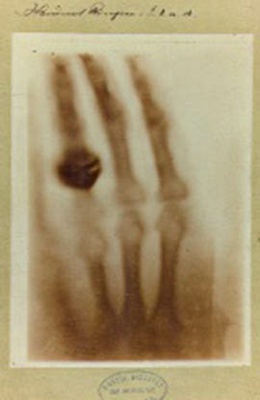

La trepanación es una de las hazañas médicas más notables de nuestros antepasados, siendo verdaderamente asombroso que los pacientes sobrevivieran a esta intervención. La existencia de cuerpo calloso en los bordes irregulares del orificio es una prueba irrefutable de supervivencia